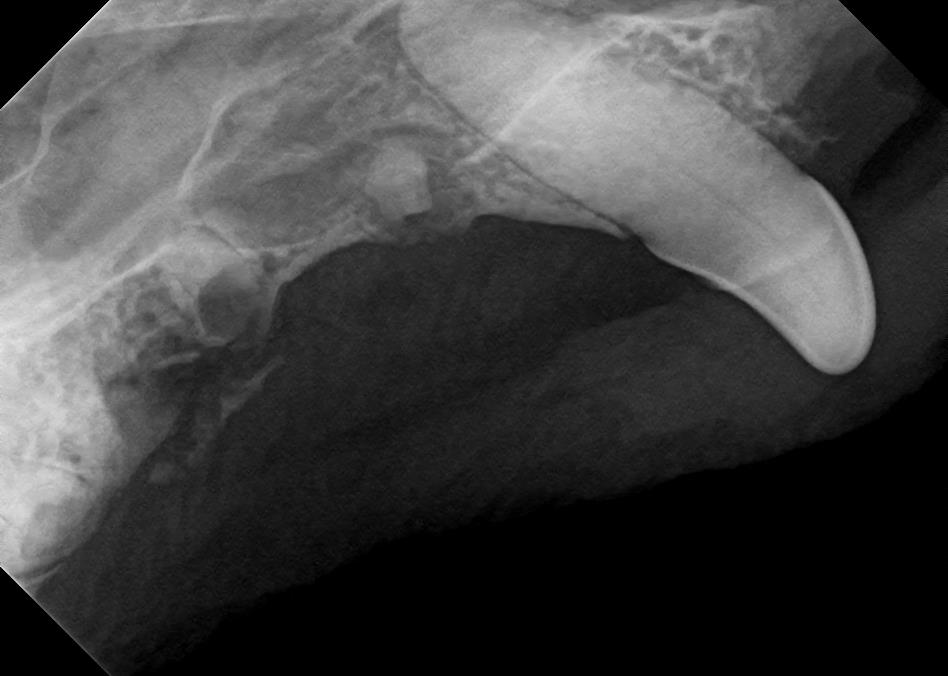

Examples of dental problems:

At A Couple of Vets, our animal hospital staff is well-versed in the latest dental cleaning techniques to remove plaque and tarter from the teeth’s surface as well as from below the gum line. We perform dental x-rays at every cleaning to ensure that the teeth are completely healthy. They may look good on the surface, but many problems occur below the gum line and are only visible with x-rays.